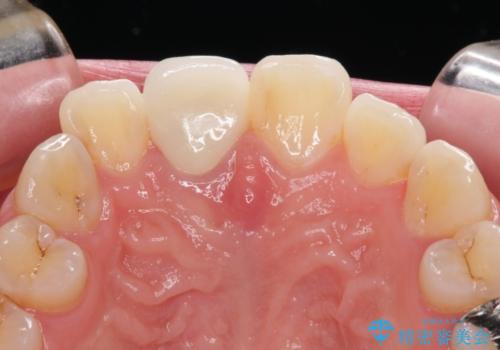

根管治療された状態に大きな問題はなかったため、土台を植立し、オールセラミッククラウンにて補綴治療を行うこととしました。

オーダーメイドタイプのクラウンを選択されたため、周辺の歯と調和が取れる色合いとなるまで修正を繰り返しました。